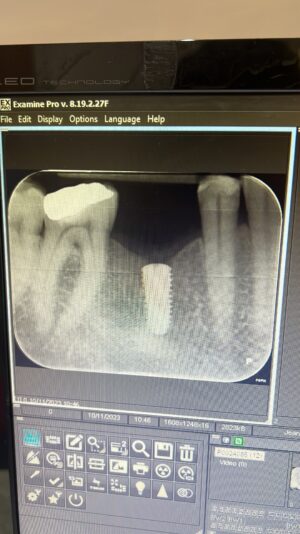

• Hello everyone,

These are osstem bone level implants which i placed 3 months ago. Upper right first premolar was immediate after extraction with grafting in the gap. 3 months after you can see some slight bone loss especially mesially of the upper premolar implant, would like to know the cause and how to prevent this? Also if implants are…

Read more

• For the upper pre-molar, potentially, it may not have been deep enough. The x-ray does look like it could’ve been deep enough, but if there was some buccal or Palatal bone loss on the mesial then it may had to have been slightly deeper to compensate for that and if there’s too much bone loss on either of those walls, it would definitely be…

• Another thing to consider is the proximity to the tooth anterior tooth. Did the anterior teeth have any perio-disease? Studies show that disease from neighboring teeth can extend up to 2mm outwards. This might be something to consider. Thanks for sharing!